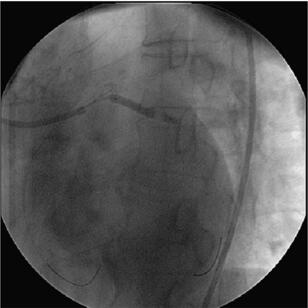

冠状动脉造影(图058‐2、图058‐3)多体位造影显示:冠脉呈右冠优势型,L M开口见90%局限性狭窄;LAD 管壁不光滑,近段见90%局限性狭窄,D1 开口后次全闭塞,中段见85%弥漫性病变,远端血流TI MI 3 级;LCX 管壁不光滑,远端90%局限性狭窄,OM1分叉处Ⅰ型分叉病变,最窄处约80%,远端血流TI MI 3 级;RCA 管壁欠光滑,远段见85%偏心性狭窄,PDA 开口前分叉病变,最窄处约95%,远端血流TI MI 3 级。

图058‐2 冠状动脉造影

图058‐3 冠状动脉造影